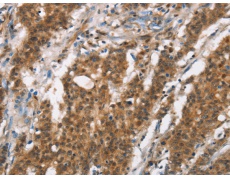

IHC positive control: |

Human gastic cancer and Human thyroid cancer |

IHC Recommend dilution: |

50-200 |